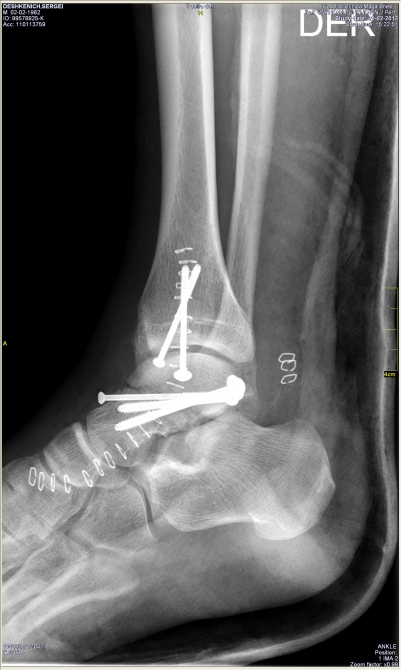

А дальше: бесконечный спуск, попытки вызвать вертолет, разборки со страховой (можно написать отдельную статью про мытарства), госпиталь, операция, длительное восстановление... Диагноз — перелом со смещением таранной кости и осколочно лодыжки. Что будет дальше? Поживем — увидим.